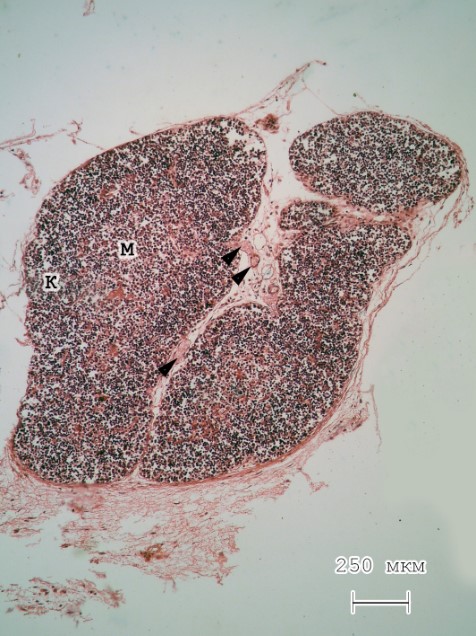

При гистологическом исследовании на малом увеличении видно, что дольки тимуса имеют овальную форму. Количество септ незначительно. В пределах последних, а также между долями тимуса, хорошо определяются сосуды и небольшое количество жировой ткани. Исследование на светооптическом уровне тимуса крыс обеих групп показало, что граница между корковым и мозговым веществом плохо выражена. При этом все же видно, что центр долек окрашивается менее интенсивно в сравнении с их периферическими отделами (рис. 1, 2).

Рис. 2. Тимус новорожденной крысы группы ФА. Объектив – х4. Гематоксилин и эозин

Примечания: граница между корковым и мозговым веществом определяется более четко в сравнении с контролем; К – корковое вещество; М – мозговое вещество; стрелки указывают на кровеносные сосуды